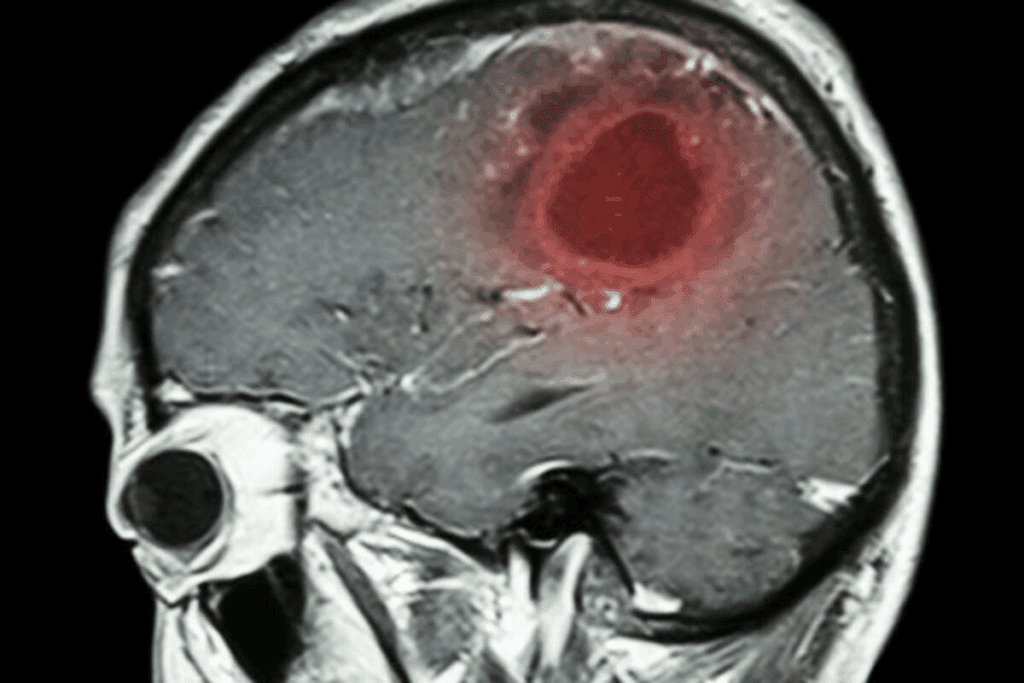

Imaging Techniques: MRI, CT, and PET Scans

Imaging is key in finding brain tumors. Magnetic Resonance Imaging (MRI) shows soft tissues well, perfect for tumors. Computed Tomography (CT) scans are fast but use radiation. Positron Emission Tomography (PET) scans show how tumors work, helping doctors decide on treatment.

But, these tools have downsides. MRI and CT scans are expensive and not everywhere. PET scans use radiation and are used in certain cases. Also, reading these images needs special skills, and results can vary.

We need better, less scary ways to find brain tumors. Blood tests might be the answer. Comparing “MRI vs blood test tumor” or “ct scan vs blood test brain” is getting attention as blood tests’ role grows.

Using both neuroimaging and blood tests could change how we find brain tumors. This mix could lead to better, earlier detection. It’s not about picking one over the other but finding the best way to help patients.